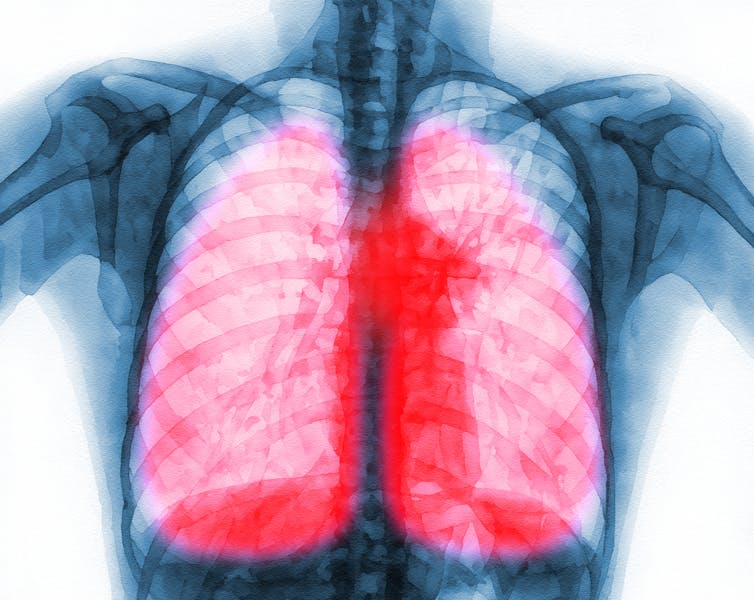

Out team wanted to better understand the long-term effects of COVID-19 on the respiratory system. To do this, we worked to identify key features associated with lung scarring following COVID-19.

First, we examined lung samples from patients with long COVID-19. Although these patients were infected several months to years before the samples were taken, we found evidence of an overactive immune system in their lungs, particularly within areas that failed to fully repair themselves after infection.

Using our new mouse model, we were able to identify the presence of an abnormal cluster of cells in mice lungs – made up of the same dysfunctional immune and epithelial, or structural, cells seen in the lungs of long-COVID-19 patients. Additionally, we found that the uncontrolled activity of these immune cells in the lungs impeded structural cells from repairing themselves. It also hindered them from restoring gas exchange, the process of taking in oxygen and releasing carbon dioxide.

Importantly, when we blocked the activity of proteins associated with this overactive immune response, it reduced lung scarring and restored optimal lung function in mice.